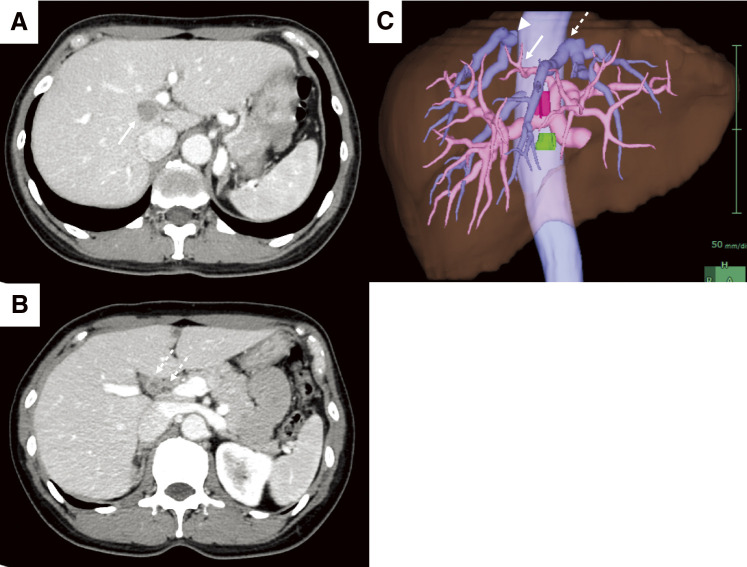

Case presentation: A 52-year-old woman was referred to our hospital and was subsequently diagnosed with bilateral breast cancer. Computed tomography (CT) and magnetic resonance imaging incidentally detected a liver tumor in the hilar region and lymph node enlargement in the hepatoduodenal ligament. A 19 mm tumor was observed in the area surrounded by the right and left branches of the portal vein and an abnormal portal branch of segment 7. Positron emission tomography-CT showed fluorodeoxyglucose uptake in the liver tumor, hepatoduodenal ligament lymph nodes, and bilateral breasts. A tumor biopsy showed a papillary tumor, and ICC was suspected. As ICC with LNM has a poor prognosis, neoadjuvant chemotherapy was planned. Genetic testing using a blood sample revealed a BRCA2 mutation, indicating the patient would benefit from chemotherapy, particularly cisplatin. The patient received a chemotherapy regimen comprised of gemcitabine, cisplatin, and S-1 (GCS), and after 7 courses, her carbohydrate antigen 19-9 level decreased from 2433 to 15 U/mL. CT showed that the tumor had shrunk and the LNMs were indistinct. The patient was referred to our department for curative surgery, which included a left hepatectomy, caudate lobectomy, hepatoduodenal ligament lymph node dissection, bile duct resection, and choledocojejunostomy. The postoperative course was generally uneventful, and the patient was discharged on postoperative day 18. Pathological examination of the resected specimen revealed an absence of malignant cells. At 24 months postoperative, there was no evidence of recurrence.